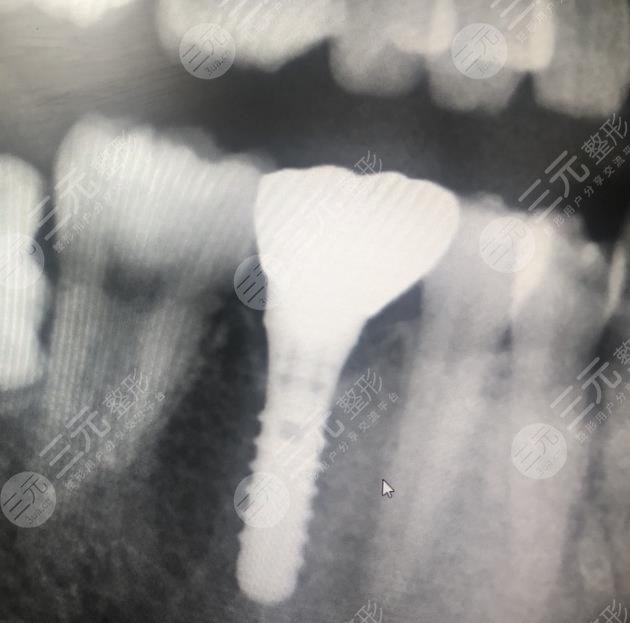

三、上海牙防所种植牙手术案例分享

手术之前:我是一个很爱美的人,可是却因为牙齿磕掉了一颗,所以显得特别的不好看,而且还是在前门牙的部位,这种情况让我感到特别的自卑,有的时候不知道该用什么方法去解决,就在较近几年很多人都在说,现在医院里边特别流行有一种叫种植牙手术的,不知道管不管用,我想去医院尝试一下,那天来到医院和这里的整形专家沟通了一下,把我想知道的都问了一下医生,医生也中和我的实际情况为我设计了手术的方法,整个手术在缓解的过程中大概只用了三个小时。

手术当中:在手术完成之后,医生让我在医院多呆几个小时观察一下是不是有什么不良的情况,在医院观察了几个小时之后,并没有发生任何的不良情况,我就回家了,回家之后我和医生一直保持着沟通,有什么不懂的都会及时的问医生,医生也会告知我,就这样手术大概过了有8个月左右的时间我的牙齿就恢复了,现在的牙齿和天生的根本看不出什么区别来,而且特别的坚固,在这期间牙齿也没有出现松动,吃什么东西都不妨碍,我真的是好开心很感谢这家医院的医生。